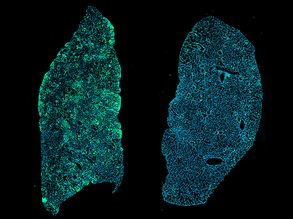

Capturing Lung Development

23